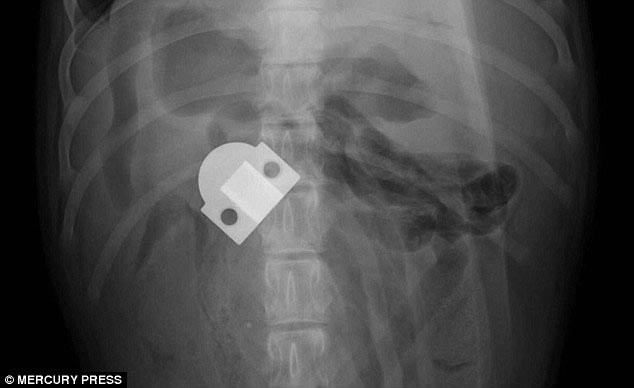

3 место - 6-месячный лабрадор-ретривер Эвери, который съел шарнир от двери

![Что на ужин? Рентгеновские снимки животных, с шокирующими предметами извлеченными из их желудков предметы извлеченные из желудков животных, рентгеновские снимки животных съевших предметы, необычные предметы съели животные]()